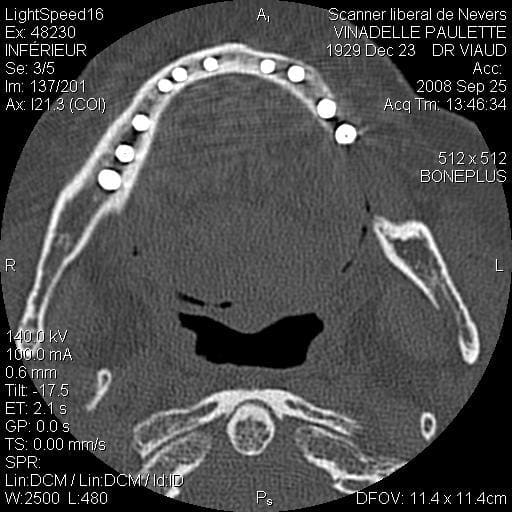

Je suis désolé mais le seul problème que j’ai eu sur un maxillaire inférieure (celui que j’ai mis en photo d’ailleurs) c’est une rupture de la table interne en 33 34 (suite à un mouvement inopportun de la patiente, ce que j’aurais du prévoir) j’ai repris le cas 3 mois plus tard et no problème.

scan te montrant la façon dont je contourne les obstacles